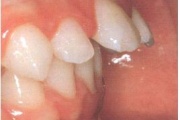

Ravijärgne seis. Jäävhammas on täielikult lõikunud.

) Röntgenülesvõte. Ülemise esimese jäävmolaari lõikumine on takistatud 2. piimamolaari tõttu

Esimese jäävmolaari ektoopiline lõikumine